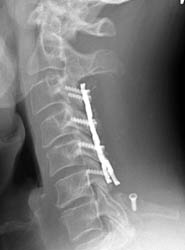

Screw Displacement

50-year-old male who presented with worsening gait, neck pain, upper

extremity pain, numbness, and occasional bowel and bladder incontinence. The

patient complained of increasing difficulty walking, neck stiffness, and leg

cramps, increasing upper extremity numbness, and dysthesia in hands and

forearms. The patient underwent C3-6 laminectomies with postero-lateral fusions.

AP and lateral radiographs taken 5 days after surgery demonstrate

typical laminectomy defects at C3-6. The posterolateral fusions appear intact

with bone grafting material faintly appreciated. The screws and plates are

intact and in appropriate positioning. |

AP and lateral radiographs taken 5 days later, while still in the

hospital. Note migration of left C6 screw. It has loosened and fallen out. This

screw was not causing symptoms and decision was made to conservatively manage

the patient and keep in rigid cervical collar until the bone graft matured in

2-3 months.